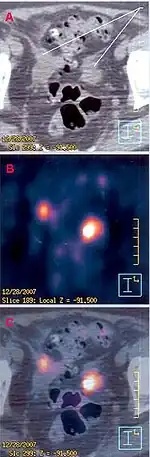

A complete body PET–CT fusion image | |

Positron emission tomography–computed tomography (better known as PET–CT or PET/CT) is a nuclear medicine technique which combines, in a single gantry, a positron emission tomography (PET) scanner and an x-ray computed tomography (CT) scanner, to acquire sequential images from both devices in the same session, which are combined into a single superposed (co-registered) image. Thus, functional imaging obtained by PET, which depicts the spatial distribution of metabolic or biochemical activity in the body can be more precisely aligned or correlated with anatomic imaging obtained by CT scanning. Two- and three-dimensional image reconstruction may be rendered as a function of a common software and control system.[1]

A whole body scan, which usually is made from mid-thighs to the top of the head, takes from 5 minutes to 40 minutes depending on the acquisition protocol and technology of the equipment used. FDG imaging protocols acquires slices with a thickness of 2 to 3 mm. Hypermetabolic lesions are shown as false color-coded pixels or voxels onto the gray-value coded CT images. standardized uptake values are calculated by the software for each hypermetabolic region detected in the image. It provides a quantification of size of the lesion, since functional imaging does not provide a precise anatomical estimate of its extent. The CT can be used for that, when the lesion is also visualized in its images (this is not always the case when hypermetabolic lesions are not accompanied by anatomical changes).